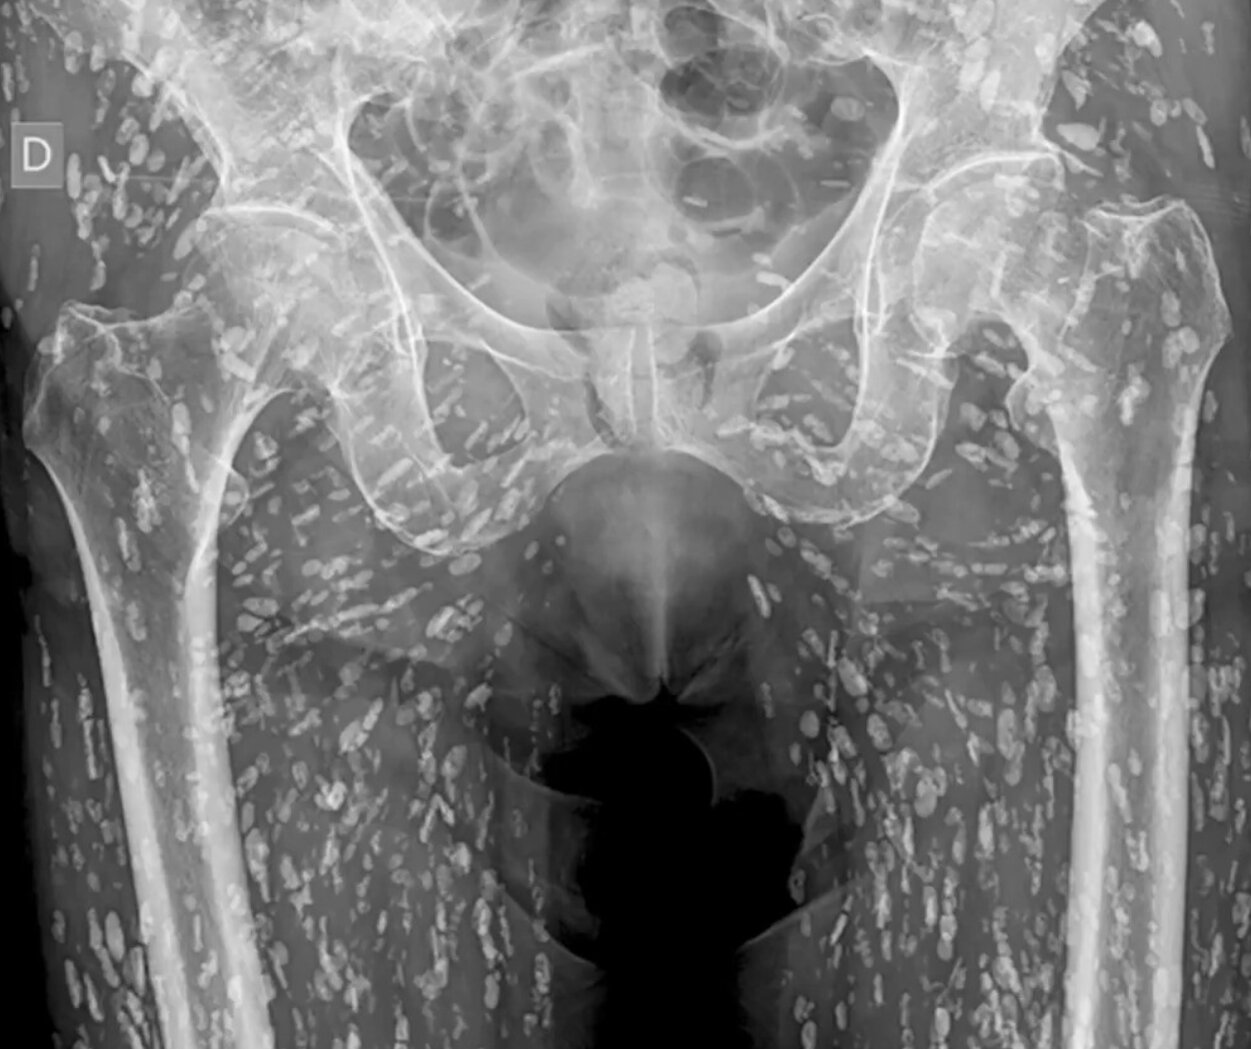

Một ca chụp X-quang tưởng chừng b́nh thường sau cú ngă lại bất ngờ hé lộ hàng trăm nang kư sinh đang trú ngụ khắp phần thân dưới của bệnh nhân. Điều gây sốc hơn cả là nguyên nhân đến từ một thói quen ăn uống phổ biến nhưng tiềm ẩn rủi ro lớn.

Một bức ảnh chụp X-quang kỳ dị, cho thấy cơ thể bệnh nhân chứa đầy nang sán dây đă trở thành chủ đề gây sốc trên mạng xă hội X (Twitter cũ), sau khi được bác sĩ cấp cứu Sam Ghali chia sẻ cùng lời cảnh báo: “Đây là một trong những phim X-quang điên rồ nhất mà tôi từng thấy.”

Trong h́nh ảnh, toàn bộ phần thân dưới của bệnh nhân, từ hông đến chân, xuất hiện chi chít những mảng trắng h́nh thoi như mưa đá bên trong cơ thể. Bác sĩ Ghali xác nhận đây là biểu hiện điển h́nh của bệnh ấu trùng sán dây heo, tên khoa học là cysticercosis, do loài kư sinh trùng Taenia solium gây ra.

“Cơ thể bệnh nhân này bị nhiễm đầy nang ấu trùng của sán dây heo, thứ mà chúng tôi thường gọi là ‘canxi hóa hạt gạo’ v́ h́nh dạng đặc trưng trên X-quang,” bác sĩ Ghali giải thích.

“Đây là một trong những phim X-quang điên rồ nhất mà tôi từng thấy", bác sĩ Sam Ghali chia sẻ. (Ảnh: @EM_RESUS/X)

Ông cho biết bệnh nhân bị nhiễm sau khi ăn thịt heo sống hoặc chưa được nấu chín kỹ. Tuy nhiên, điều nguy hiểm không nằm ở việc ăn sán trực tiếp, mà ở việc nuốt phải trứng sán – thường qua đường phân-miệng, khi người nhiễm không rửa tay sạch sau khi đi vệ sinh hoặc sử dụng nguồn nước bị ô nhiễm.

“Ṿng đời của sán bắt đầu khi một người ăn phải thịt heo chưa chín có chứa nang sán. Con sán trưởng thành phát triển trong ruột và đẻ trứng. Nếu trứng này truyền sang người khác qua tiếp xúc phân-miệng, người đó sẽ bị nhiễm cysticercosis,” Ghali giải thích thêm.

Ở bệnh nhân nói trên, các nang sán không xâm nhập vào năo mà chỉ nằm ở phần mô mềm quanh hông và chân, nên không gây nguy hiểm tức th́. Trớ trêu thay, bức X-quang chỉ được chụp sau khi người này bị ngă và găy xương, hoàn toàn không liên quan đến triệu chứng kư sinh trùng.

“Mặc dù nh́n rùng rợn, các nang sán ở phần cơ thường không gây biến chứng ngay. Nhưng nếu chúng di chuyển lên năo, hậu quả có thể nghiêm trọng hơn nhiều,” bác sĩ cảnh báo.

Trong trường hợp ấu trùng di chuyển vào hệ thần kinh trung ương, người bệnh có thể mắc bệnh sán năo (neurocysticercosis) , dẫn đến triệu chứng như đau đầu kéo dài, lú lẫn, động kinh và thậm chí tử vong nếu không điều trị.

Theo Tổ chức Y tế Thế giới (WHO), mỗi năm có khoảng 2,8 triệu người trên toàn cầu bị nhiễm sán dây heo, với số ca bệnh tập trung tại châu Á, Nam Mỹ và Đông Âu. Các chuyên gia y tế cảnh báo rằng t́nh trạng mất vệ sinh, thực phẩm kém an toàn và thói quen ăn thịt tái là nguyên nhân chính gây lây nhiễm.

“Lời khuyên của tôi là: hăy giữ vệ sinh tốt nhất có thể, luôn rửa tay sạch sẽ và tuyệt đối đừng ăn thịt heo sống hoặc chưa nấu chín,” bác sĩ Ghali nhấn mạnh trong phần kết thúc bài đăng.